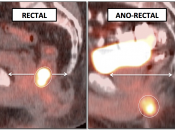

- Hemorrhoids are often intensely avid in the ano-rectal region (and are usually not visible on the CT images). Be certain that uptake does not lie more superiorly in the rectum. Additionally, carefully assess for an accompanying soft tissue density to exclude an anal cancer.

- Beware the small rectal cancer! As the ano-rectal region frequently demonstrates intense physiologic uptake, it is very easy to overlook a rectal malignancy, especially if it is an incidental finding. To avoid this error, always evaluate the rectum carefully on the sagittal whole body images. It is shocking to see how readily apparent a rectal cancer can be on these images, yet so easily overlooked in the axial plane.